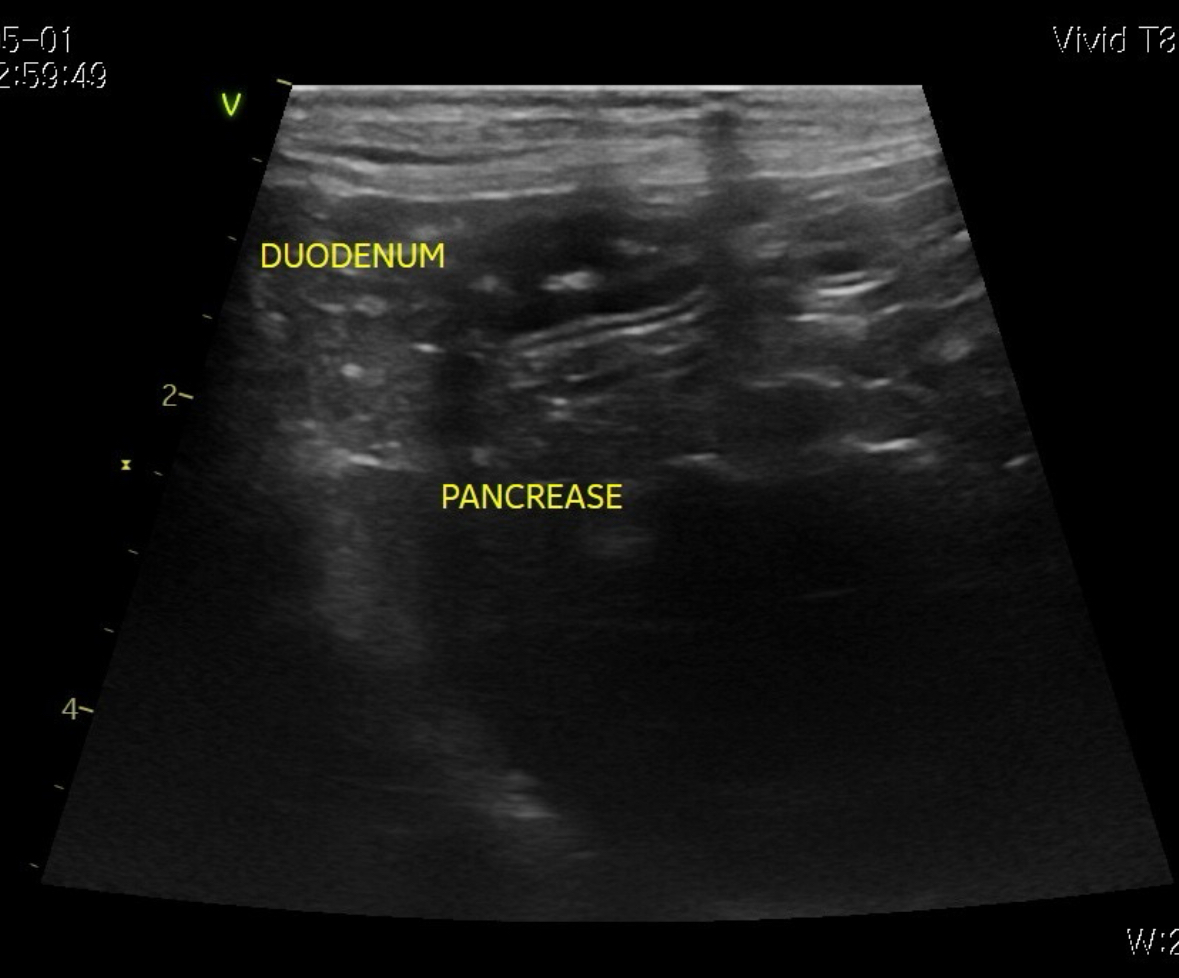

[초음파]